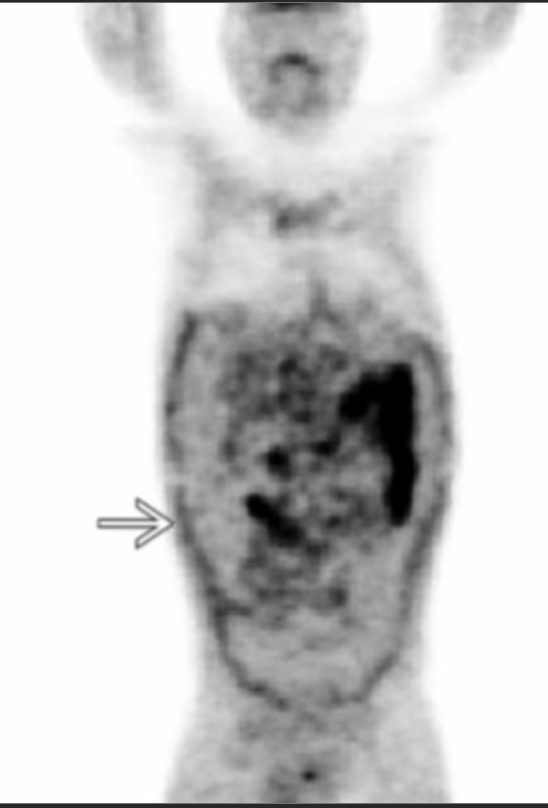

Metformin use

• Causes uptake of glucose within the bowl

• Will be see as intense FDG avidity throughout the bowel

• Doesn’t have to be seen in all parts of the bowel but will be relatively dense for a significant portion

• Affects both small and large bowel

• DDx:

• Colitis - not as continuous